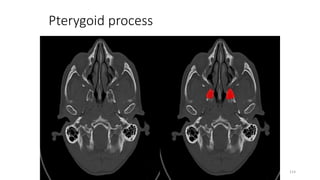

PTERYGOID PROCESS